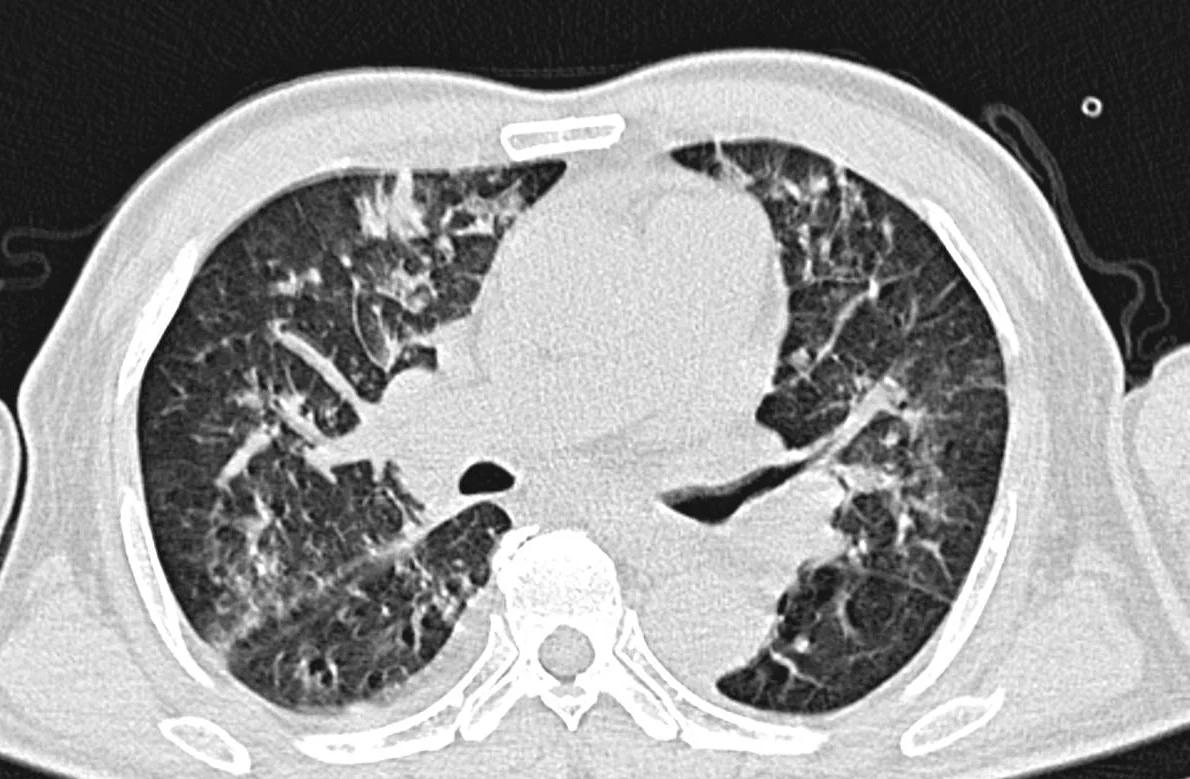

急性左心衰竭的临床表现主要包括以下几点呼吸困难劳力性呼吸困难在日间行走或活动量增加时出现夜间阵发性呼吸困难在夜间睡眠中憋醒,需要坐起才能缓解端坐呼吸平卧时很快出现呼吸困难,需要坐起或半卧位高枕卧位才能保证基本呼吸乏力与虚弱由于左心衰竭导致的灌注不足,患者会感到明显的。

一般体征 呼吸急促患者活动后呼吸急促,严重时可能出现发绀 脉压减小与脉搏加速动脉收缩压降低,脉搏加速 外周血管反应四肢末端苍白冰冷,指趾发绀 窦性心动过速与心律失常交感神经系统活性增高的迹象心脏体征 左心室增大急性左心衰竭的典型表现,即使在疾病早期也可能不明显 奔马。